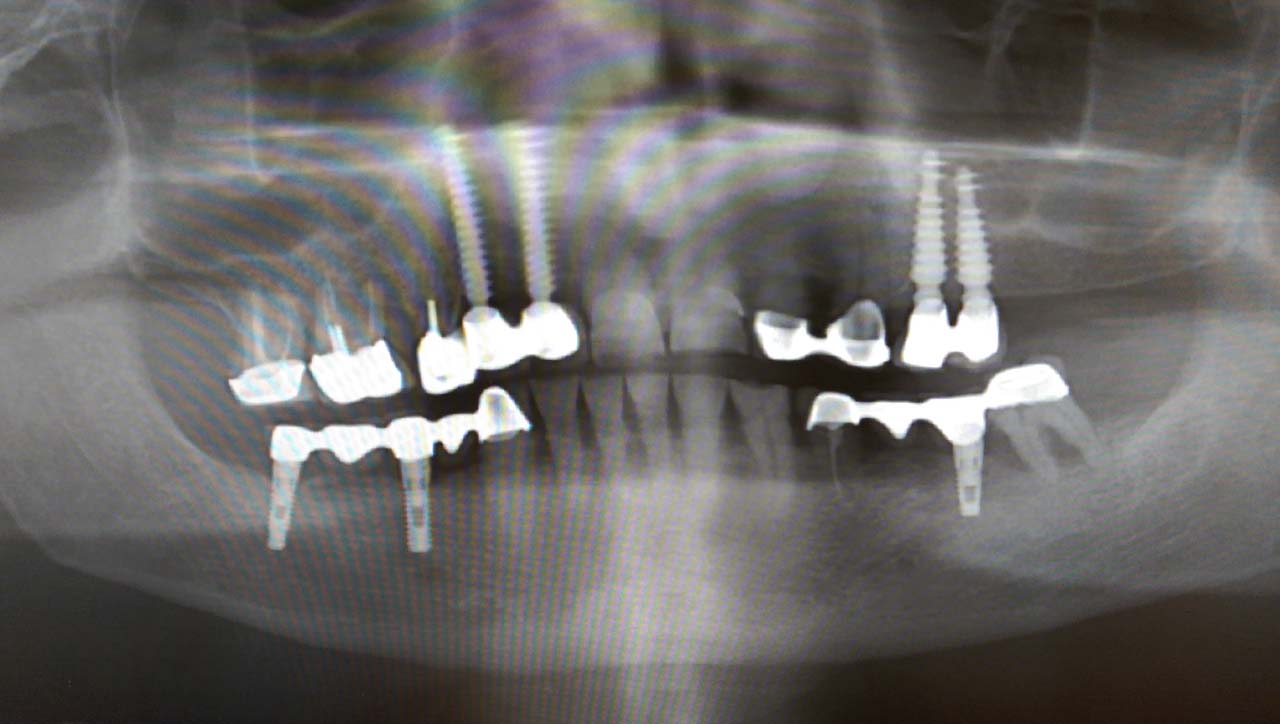

Elhanyagolt fogsor cseréje 2 nap alatt

2 nap alatt varázsoltuk ezt a szép esztétikus alsó, felső körhídat implantátumokkal megtámasztva a korábban elhanyagolt szájba. Az 1. nap 26 fogat távolítottunk el, mert annyira rossz állapotban voltak, és rögtön azonnal terhelhető IHDE svájci implantátumokat raktunk be, fentre 8, lentre 6 darabot. A sebeket összevarrtuk és intraorális szkennerrel digitális lenyomatot vettünk. 2 nap múlva pedig beragasztottuk a kész PMMA műanyag körhidakat. Dr. Kelemen Péter és a Symbion Fogtechnika munkája.